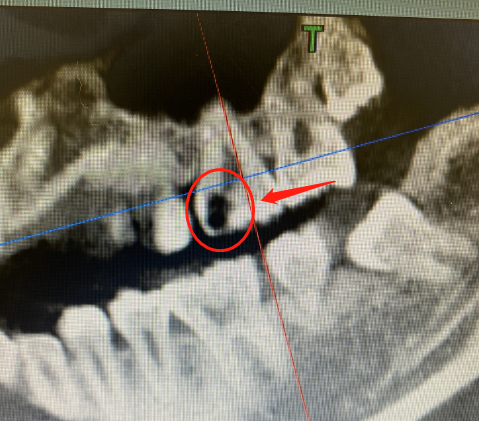

先向大家简单说明一下牙齿的构造:在牙冠部有两层组织包裹着髓腔,从外到内依次是牙釉质、牙本质、牙髓腔。

最表面的是我们看得见的釉质层(牙釉质也是我们人体最为坚硬的组织);接下来是牙本质层,它是在釉质层里面,质地稍软,包裹着髓腔一圈,保护着牙髓神经;而中间还有一个空间,布满了血管、神经,就是牙髓组织。

目前针对牙髓炎的治疗,主要是“根管治疗术”。

简单来讲,就是医生使用专业器械对根管进行清理、成形、消毒灭菌,然后严密填塞根管,从而达到控制感染、防止根尖周炎的发生或促进原有根尖周病变愈合的目的,一般治疗时间在一个半月左右,复诊次数为3-4次。